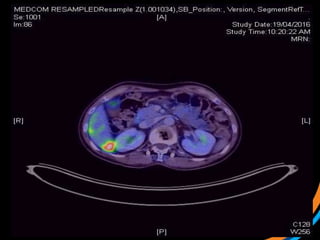

Case study 3 (Patient 009)

• 44, Female, ECOG 1

• RCC diagnosed 2007. Metastatic recurrence in 2012

• Prior RT to prevascular LN 50Gy/20# (2012)

• Started on Pazopanib, then everolimus

• Recent MRI spine shows met involving T3 and L1 vertebral body, with

involvement of superior endplate (L1)

 1) Review the images

 2) Target the lesion

T3 lesion

L1 lesion

Case study 3(Patient 009) • 44, Female, ECOG 1 • RCC diagnosed 2007. Metastatic recurrence in 2012 • Prior RT to prevascular LN 50Gy/20# (2012) • Started on Pazopanib, then everolimus • Recent MRI spine shows met involving T3 and L1 vertebral body, with involvement of superior endplate (L1)  1) Review the images  2) Target the lesion

• #35 Pre-treatment PET showing very avid disease in anterior vert body

• #38 Post RT PET at 7m The treatment effect is likely a combination of PDL1 and SBRT